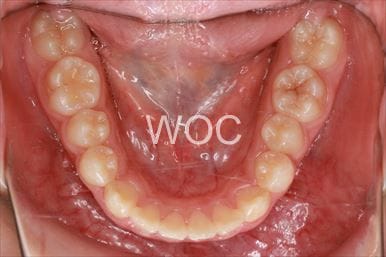

出っ歯舌側矯正

上下舌側矯正を希望。

通院状況や歯みがきの協力が良かったため、1年7ヶ月で治療を終えることができました。※装置と注意事項に関しては、大人の矯正装置一覧へ。

- 年齢:20歳女性

- 主訴:出っ歯が気になる

- 基本矯正料金:120万円

- 治療期間:1年7ヶ月

- 抜歯部位:上顎両側第一小臼歯